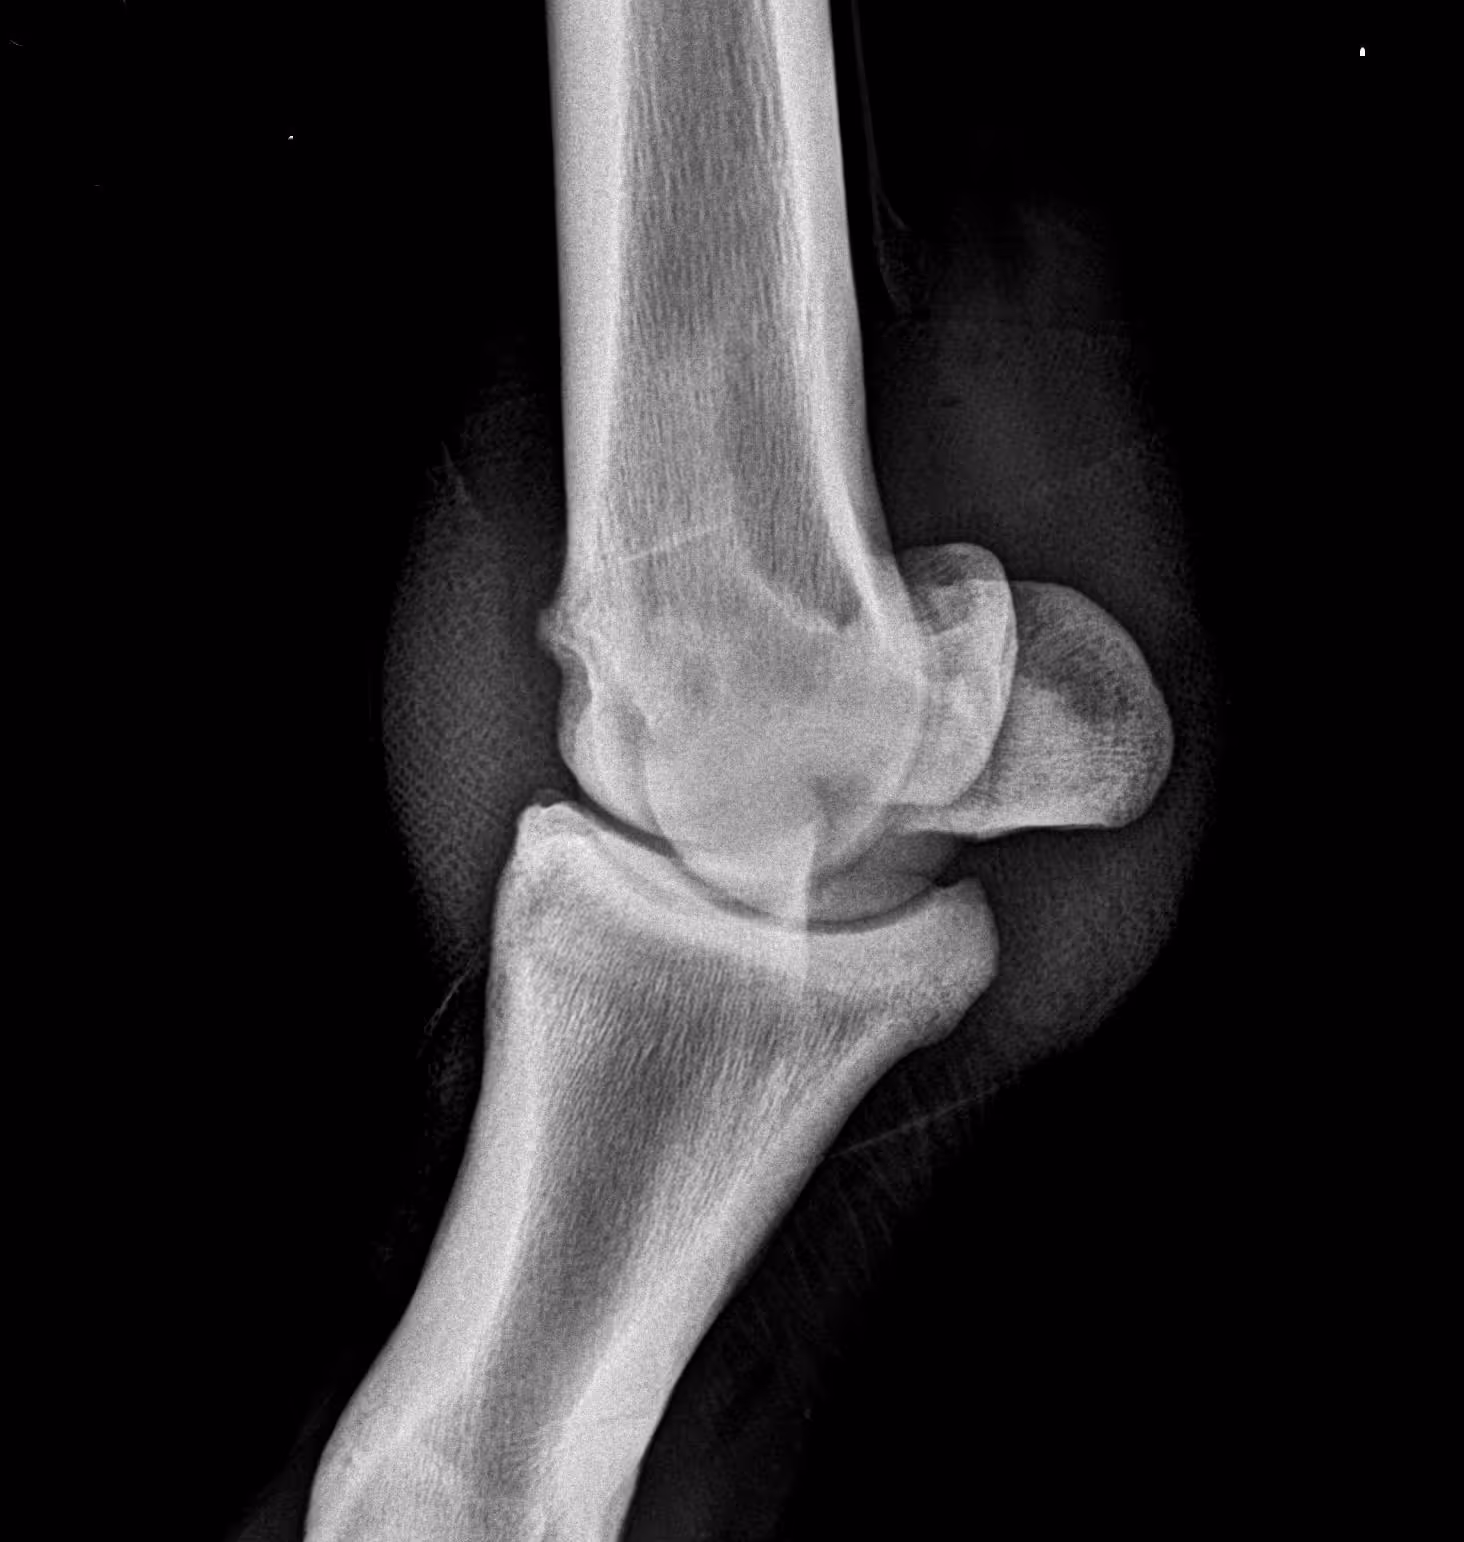

LF fetlock (LM, DLPMO, DP, DMPLO views below):

Moderate arthritis is visible as periarticular bone spurs on medial and lateral margins of P1 and MCIII. A subchondral cystic lesion is present in the medial condyle of MCIII with about 5-8mm of lost subchondral bone width. Periarticular new bone is evident at joint capsule insertions dorsally above and below the joint. Soft tissue swelling is also evident.

LM (lateromedial)